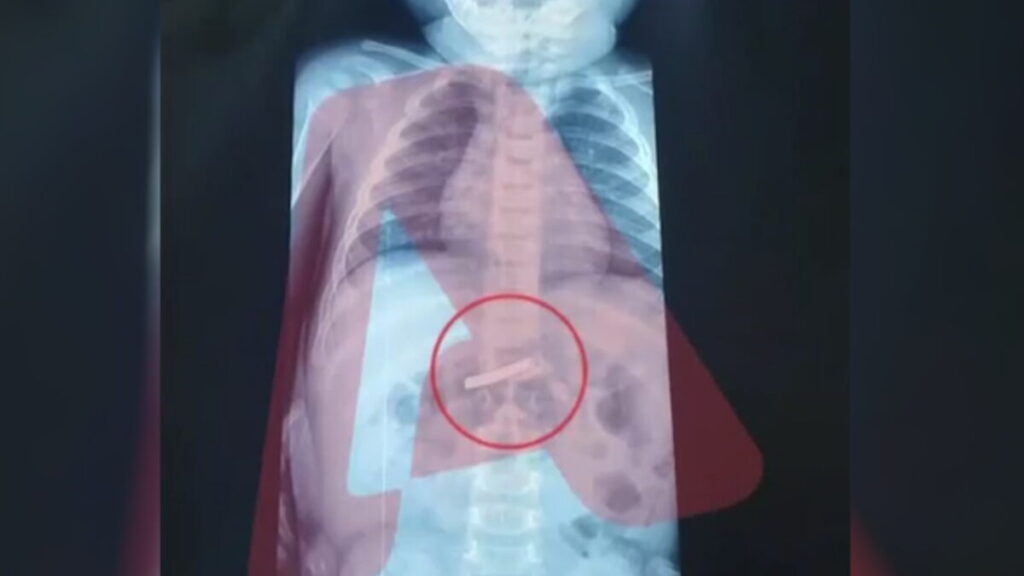

Αμέσως μετά την άφιξή του, το παιδί υποβλήθηκε σε ακτινογραφία, η οποία επιβεβαίωσε την παρουσία του αιχμηρού αντικειμένου στο στομάχι του, προκαλώντας έντονη ανησυχία στο ιατρικό προσωπικό.

Οι γιατροί ενημέρωσαν τους γονείς ότι, μέσω της ακτινογραφίας, εντοπίστηκε με ακρίβεια το σημείο στο οποίο είχε καταλήξει το ξυραφάκι. Αυτό επέτρεψε στη χειρουργική ομάδα να σχεδιάσει με προσοχή την επέμβαση, ώστε να αφαιρεθεί με ασφάλεια.